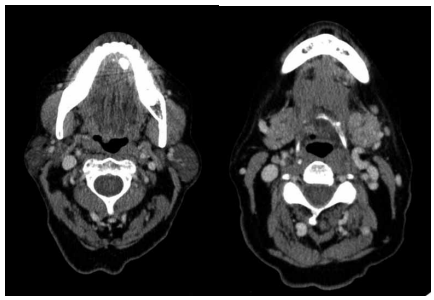

Paciente do sexo feminino, 38 anos, chega ao pronto- -socorro com queixa de dor e edema na região submandibular esquerda há dois dias. Consulte episódios semelhantes ao longo dos últimos dois anos. Exame de imagem a seguir:

(Arquivo pessoal; imagem usada com autorização)

Com base no caso descrito e nas imagens apresentadas, assinale a alternativa correta.